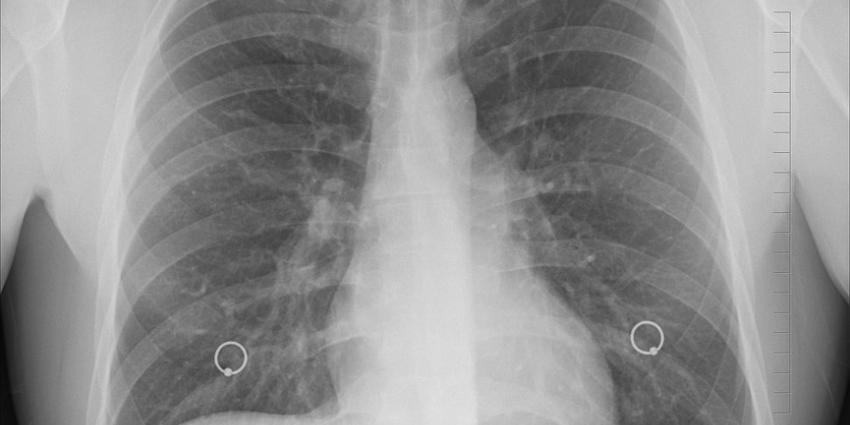

In 2018 waren er 806 tbc tuberculose -patiënten in Nederland. Dit is 3% meer dan in 2017 (784). 469 tbc-patiënten hadden longtuberculose, waarvan 204 de meest